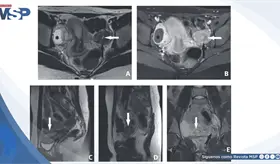

Uróloga destacó cómo la urología reconstructiva devuelve funcionalidad, bienestar y plenitud a pacientes que enfrentan secuelas físicas tras superar el cáncer.